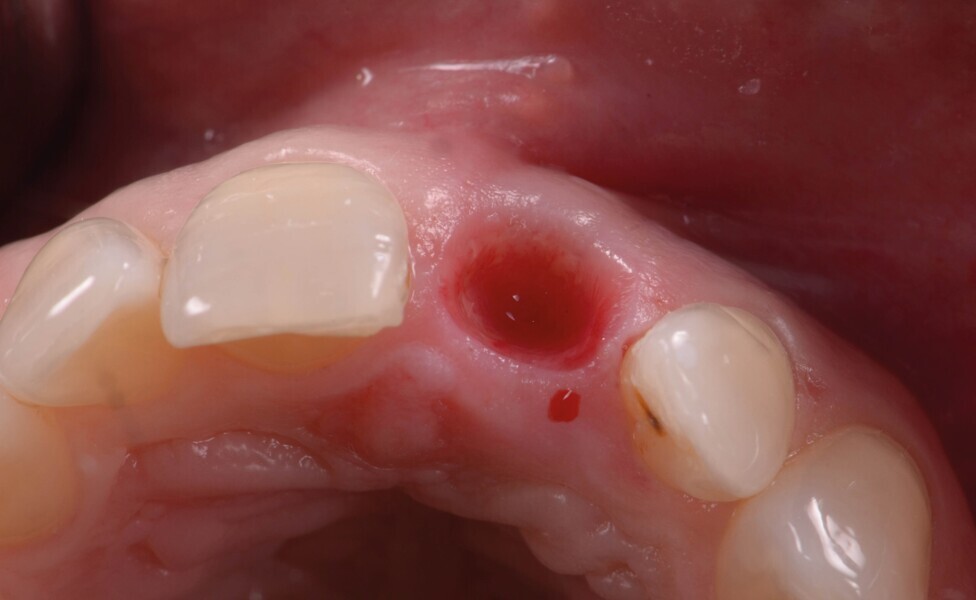

La dent 21 est extraite de la manière la moins traumatique possible à l’aide d’un périotome (Fig. 4). Elle est conservée dans du sérum physiologique afin de pouvoir l’utiliser comme restauration provisoire par la suite.

Fig. 4 : Extraction atraumatique de la dent 21.

Fig. 5a : Après l’extraction

Fig. 5b : Après l’extraction

L’alvéole est ensuite comblée par un matériau allogénique (poudre d’os PHOENIX, TBF ; Fig. 5 ) qui est légèrement compacte puis recouvert d’une membrane L-PRF pour protéger le greffon (Fig. 6). La membrane L-PRF a un rôle essentiellement mécanique qui permet de prévenir toute dispersion ultérieure du matériau de greffe dans les premières phases de la cicatrisation, jusqu’à la formation d’un caillot sanguin stable.